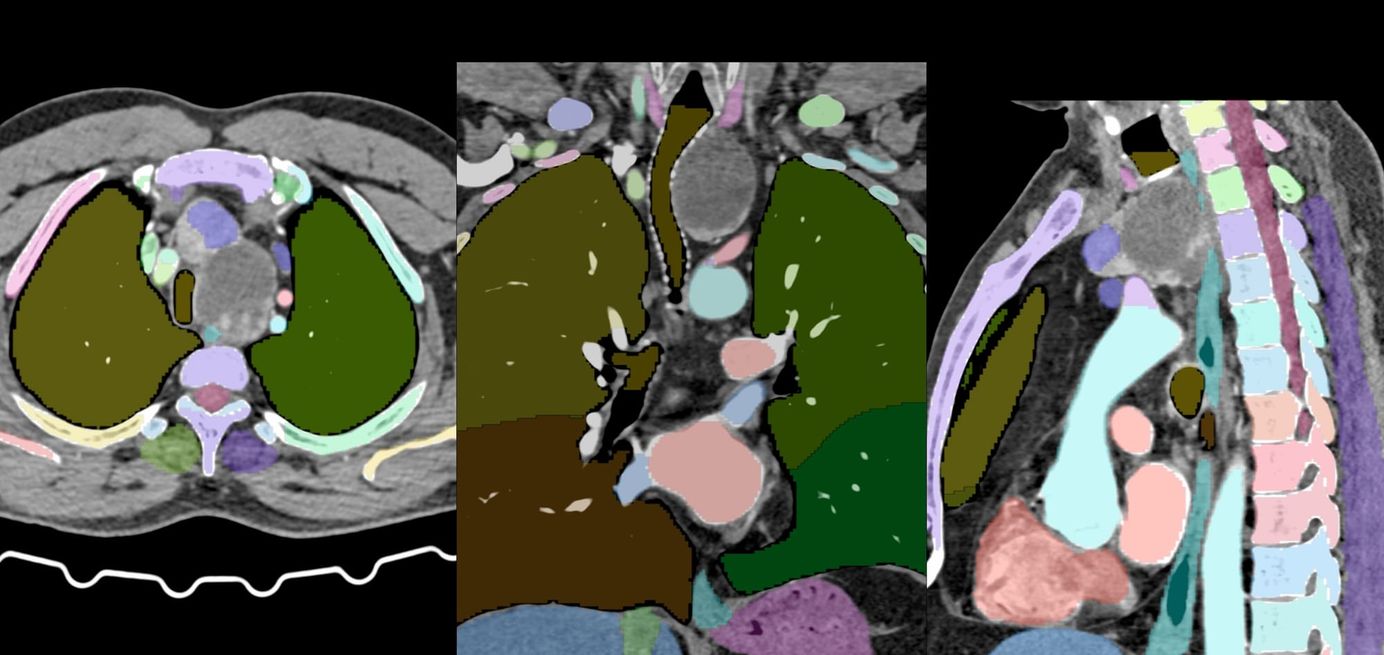

The PDIF sign is basically the presence of a fibrosing ILD typically compacted within the last 2 cm of the peridiaphragmatic lung and may suggest not just CTD-ILD but specifically myositis ILD